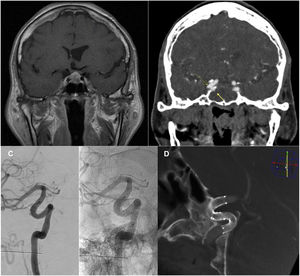

Pese a dicha revisión la paciente presentó nueva epistaxis a los 3 días, que motivó nueva revisión quirúrgica, y ante la ausencia de sangrados que la justificaran, la realización de un angio-TC (Fig. 1A) y posterior angiografía cerebral urgentes (Fig. 1B). Se objetivaron 2 imágenes compatibles con seudoaneurismas de la carótida interna derecha. Se trataron mediante microcatererización de la carótida interna derecha distal a las lesiones aneurismáticas e implantación sin incidencias de dos endoprótesis derivadoras de flujo tipo Derivo® solapadas, cubriendo el cuello de ambas lesiones, sin complicaciones. La paciente fue dada de alta tras 48h de observación con tratamiento de doble antiagregación (ticagrelor 90mg/12h y AAS 100mg/24h), sin nuevas complicaciones. Los controles a los 6 y 15 meses confirmaron la permeabilidad de los stent y la resolución de los pACI, persistiendo relleno del cuello del cavernoso, sin imágenes de hiperplasia significativa ni otras complicaciones (Fig. 1C y 1D), retirándose el tratamiento con ticagrelor. Actualmente mantiene cifras de IGF-1 dentro de la normalidad.

Macroadenoma hipofisario objetivado en RM preoperatoria (A), secuencia T1 con contraste. Angio-TC (B) diagnóstico 20 días p.o. Se identifican 2 pACI (flechas), de cuello ancho y tipo blister, en los segmentos cavernoso (medial, 3,5mm de cuello y 2,5mm de fondo, adyacente a la glándula hipofisaria) y clinoideo (bilobulado, lateral, fondo de 3 y 2,5mm, respectivamente) de la ACI derecha, que se estudiaron también mediante angiografía. C y D) Angiografía de control a los 6 meses (C) y DynaCT® de control a los 15 meses (D) postratamiento endovascular mediante la implantación de 2 stent derivadores de flujo tipo Derivo® solapados. Confirman la permeabilidad de los stent y resolución de los pACI, con permeabilidad de la arteria portadora y ausencia de signos de estenosis ni otras alteraciones intra-stent.